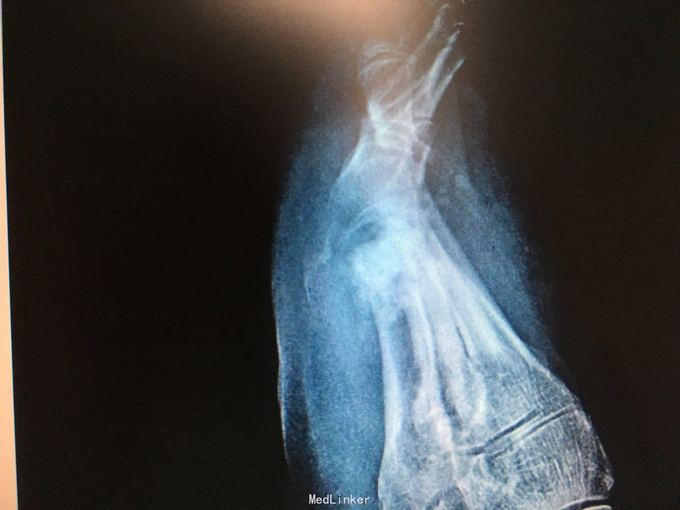

右足第一跖趾关节痛风石1例

右足第一跖趾关节肿痛加重1周

如题 手术清除

关节破坏术后石膏固定6周 术中要点:切完能切的后,9升盐水冲洗枪脉冲冲洗 术后片子在前面最后2个图了